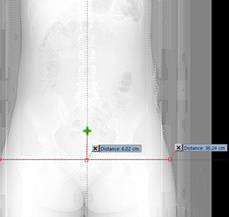

SUM Dimension: This does not require any direct measurement but is the sum of lateral and AP dimension (AP+LAT). Dimensions were derived from both localizer radiograph and 3D reconstructed data (Figure 3).

Figure 3 Measurement of AP and LAT dimension from 3D reconstructed data.